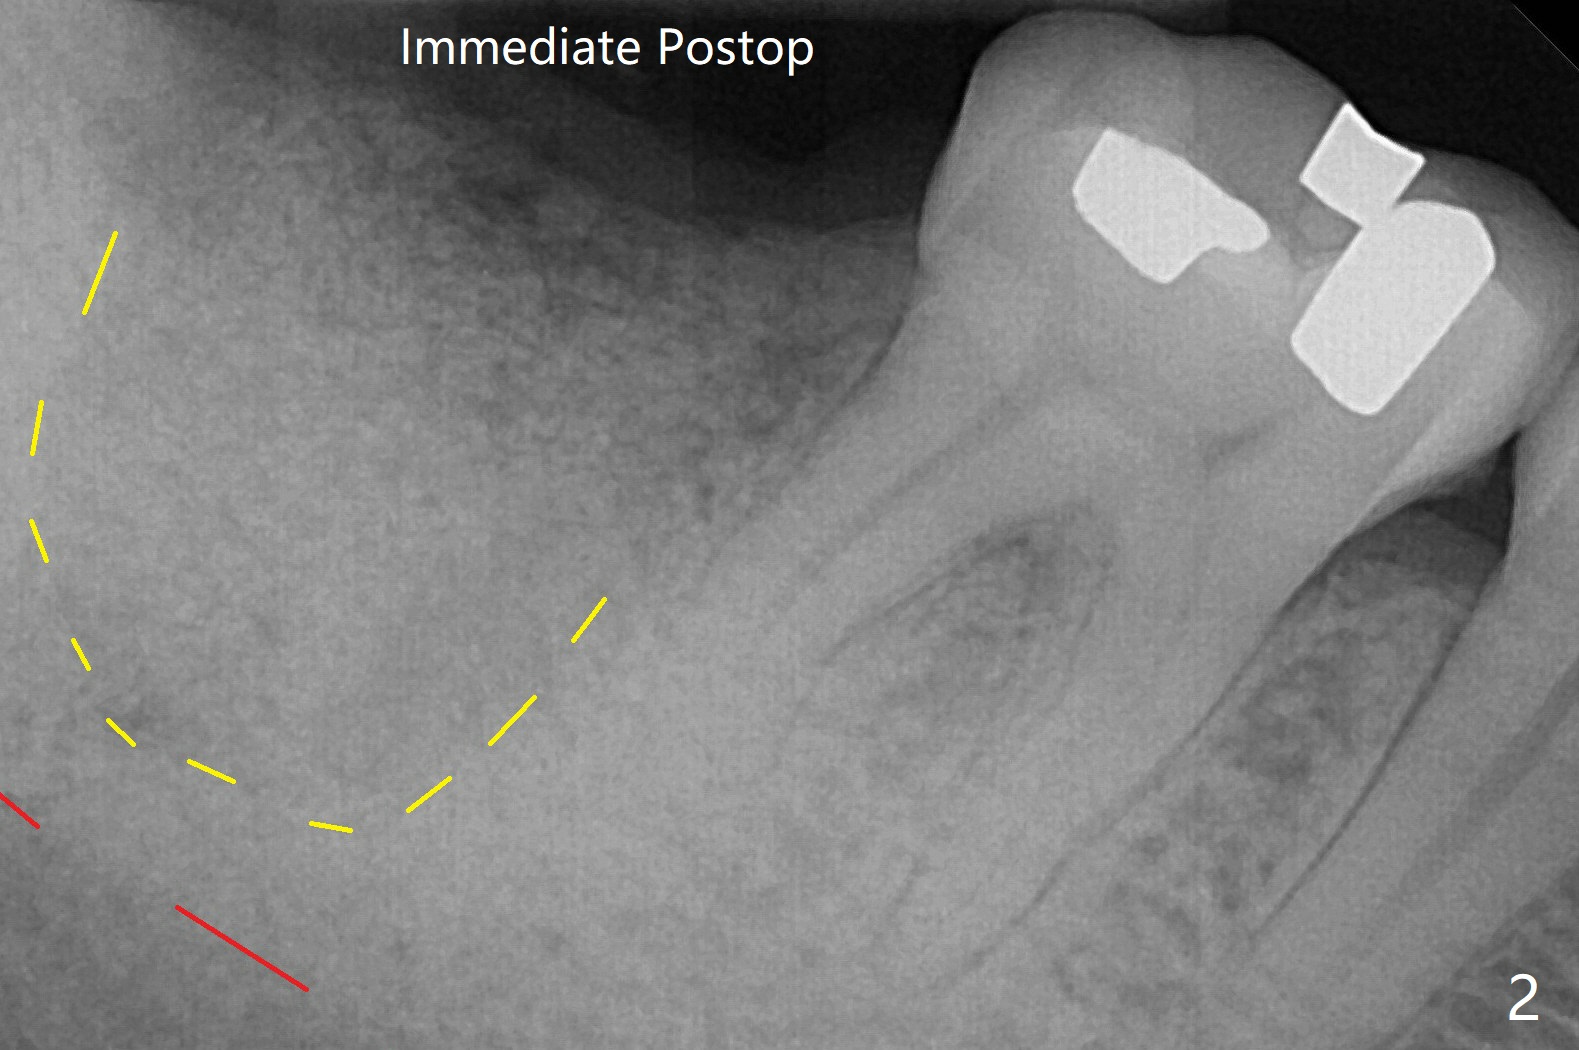

After immediate implant at #3, the tooth #31 with distal root fracture (Fig.1 *) and being close to the Inferior Alveolar Canal (red dashed line) is extracted for socket preservation (Fig.2 yellow dashed line).  Although no PRF membrane is used to cover the socket, allograft is mixed PRF liquid.  A piece of 6-month membrane is used instead.  The ridge height is maintained 6 months postop (Fig.4).